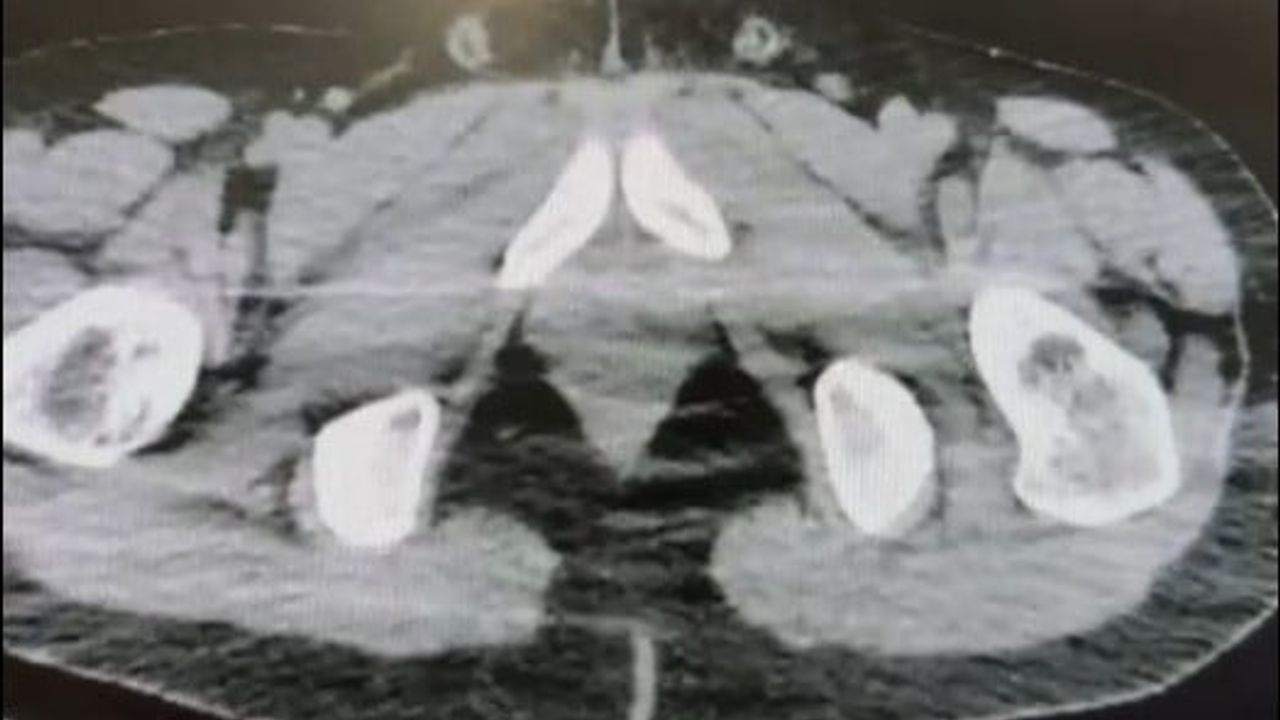

Ekiplerin sokak satıcılarına yönelik çalışmalarını yoğunlaştırması sonucu, şüpheliler S.B. ve O.R.'nin "yutma yöntemi" ile kente uyuşturucu madde sevk edeceği bilgisi üzerine operasyon düzenlendi. Şüphelilerin ikametlerinde ve araçlarında aramalar yapıldı.

Aramalarda; 101 kapsül halinde 722 gram uyuşturucu madde, 1 adet hassas terazi, yutma yönteminde kullanılan muhtelif materyaller ile uyuşturucu ticaretinden elde edildiği belirtilen 20 bin 210 TL, bin 320 euro ve 10 ABD doları ele geçirildi.